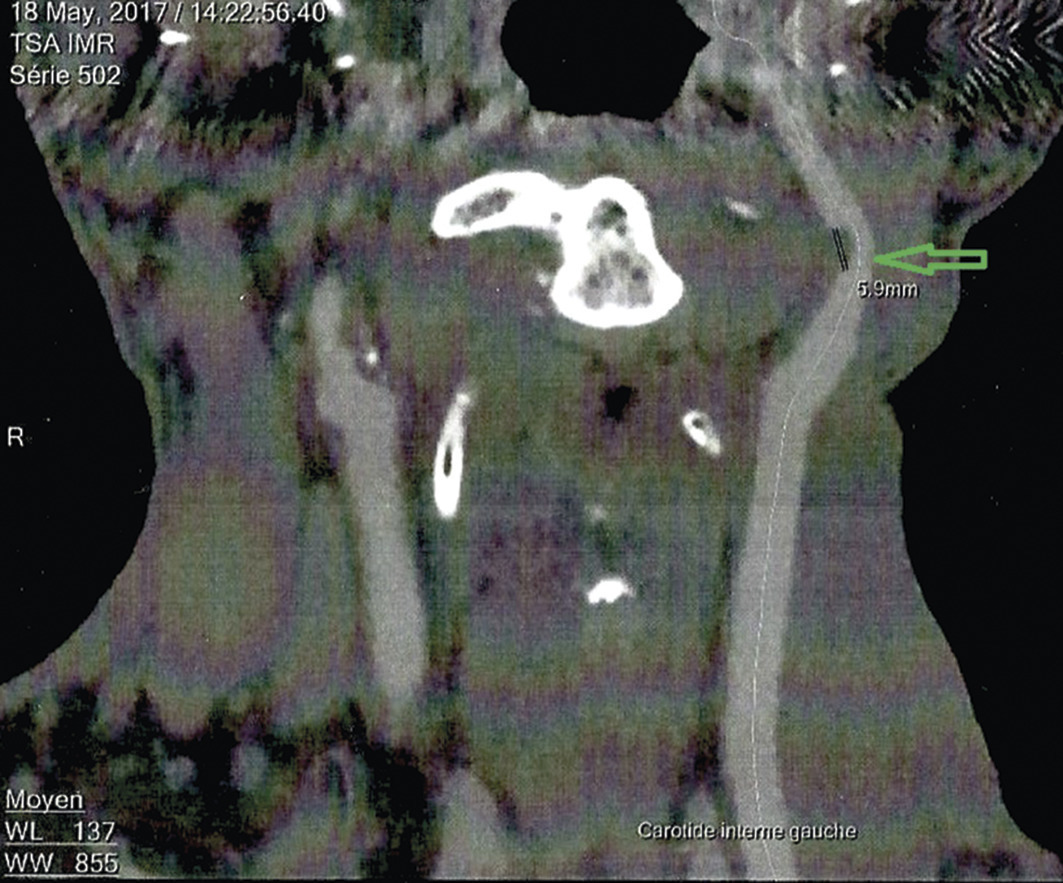

L’échodoppler des vaisseaux du cou objective une sténose de 52 % au niveau du bulbe carotidien. L’angioscanner (figure ) montre un rétrécissement à 55 % (méthode NASCET) en forme de bourgeon intraluminal, sur 6 mm, des calcifications punctiformes et des dépôts athéromateux (flèche).

L’échodoppler des vaisseaux du cou objective une sténose de 52 % au niveau du bulbe carotidien. L’angioscanner (